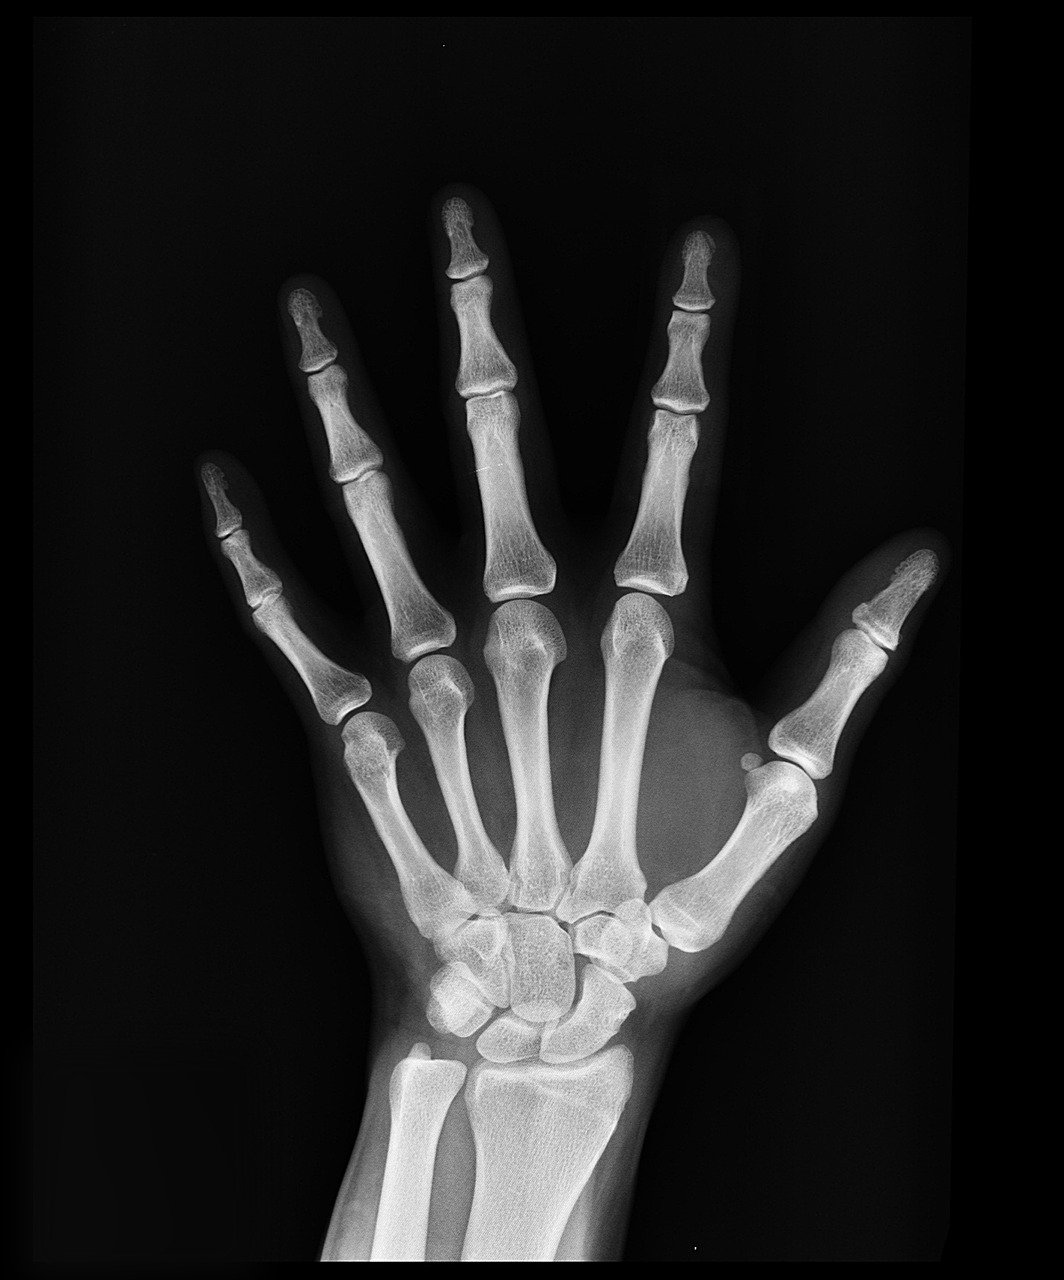

Рентгенография является одним из основных общих методов рентгенологического исследования. Ее начали применять на самых ранних этапах развития рентгенологии, вскоре после открытия рентгеновского излучения. Рентгенография позволяет получить рентгеновское изображение любой части тела. Вследствие естественной контрастности ряда тканей она является ведущим методом исследования костно-суставного аппарата, легких, сердца, диафрагмы. Рентгенография является обязательным компонентом рентгенологического исследования в условиях искусственного контрастирования органов, например ангиографии, урографии. Рентгенография имеет ряд преимуществ перед другим основным методом рентгенологического исследования — рентгеноскопией. К ним относятся: более высокое качество и детализация изображения, наличие рентгенограммы, которая может храниться с целью сопоставления с предыдущими и последующими рентгенограммами. Лучевая нагрузка на больного при рентгенографии, как правило, меньше, чем при рентгеноскопии.

Безэкранную рентгенографию (без применения усиливающих экранов) применяют редко, главным образом для изучения тонкой структуры мелких костей (например, фаланг пальцев), зубов, молочной железы.